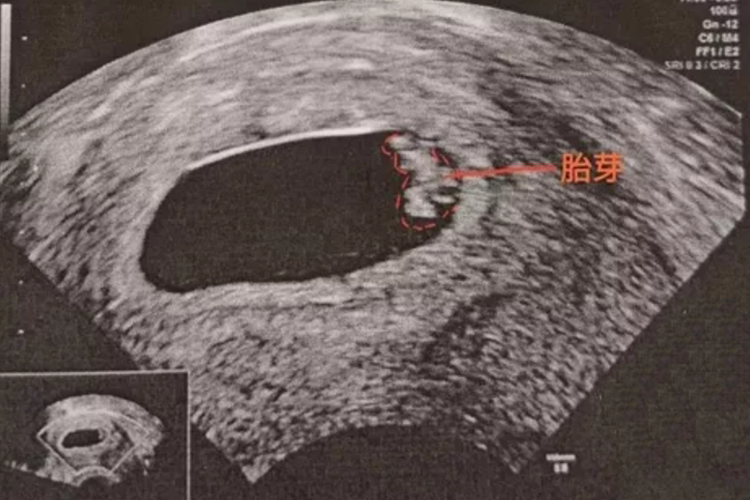

孕6-7周时B超检查可见胎芽,似“小海马”般大小。胎芽形成的阶段是怀孕关键时期,应做到定期产检、合理饮食等。

孕6-7周时通过超声检查可以看到胎芽发育,胎芽在超声上的形态类似于小海马,长约1.3cm。胎芽发育到8周末时初具人形,头大占整个胎体一半,能分辨出眼、耳、鼻、口,四肢已具雏形。